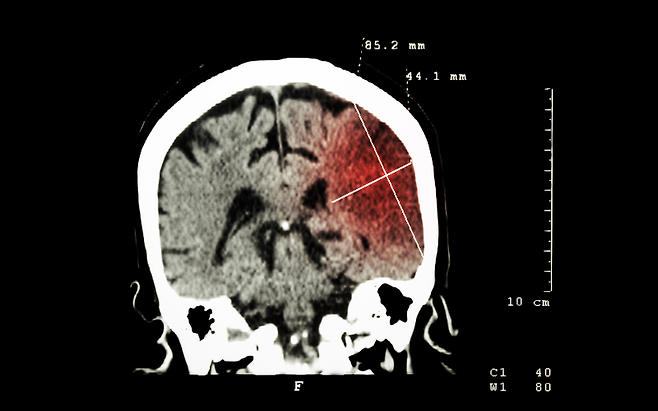

뇌경색은 갑자기 찾아오는 병처럼 보이지만, 대부분은 생활 습관의 결과입니다. 약이나 큰 치료보다 먼저 작동하는 건 아주 사소한 행동들입니다.

뇌경색을 막는 가장 쉬운 1위 습관은 자주 일어나 움직이는 것입니다. 오래 앉아 있으면 뇌로 가는 혈류가 급격히 줄고, 혈액이 끈적해지기 쉬운 환경이 됩니다.

반대로 한 시간에 한 번이라도 일어나 몇 분만 움직이면 뇌혈류가 즉각 회복됩니다. 특별한 운동이 필요 없습니다. 이 작은 움직임이 혈전 형성을 막고, 뇌경색 위험을 가장 현실적으로 낮춰줍니다.